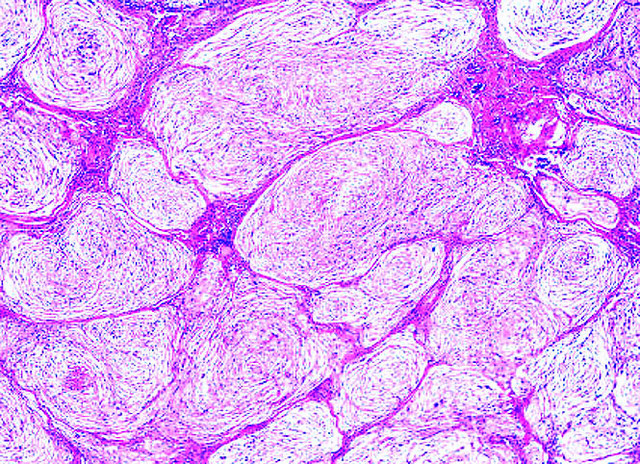

Microscopic (histologic) description

- Cellular, myxoid or mixed subtypes

- Involves dermis or subcutis

- Multinodular mass with myxoid matrix and peripheral fibrosis

- Whorled or focally fascicular patterns of spindled and epithelioid mononuclear cells with abundant cytoplasm, indistinct cell borders

- Margins usually positive; usually occasional multinucleated giant cells

- Variable nuclear atypia

- Median 4 MF / 25 HPF, may have 10+ MF / 25 HPF, may be atypical